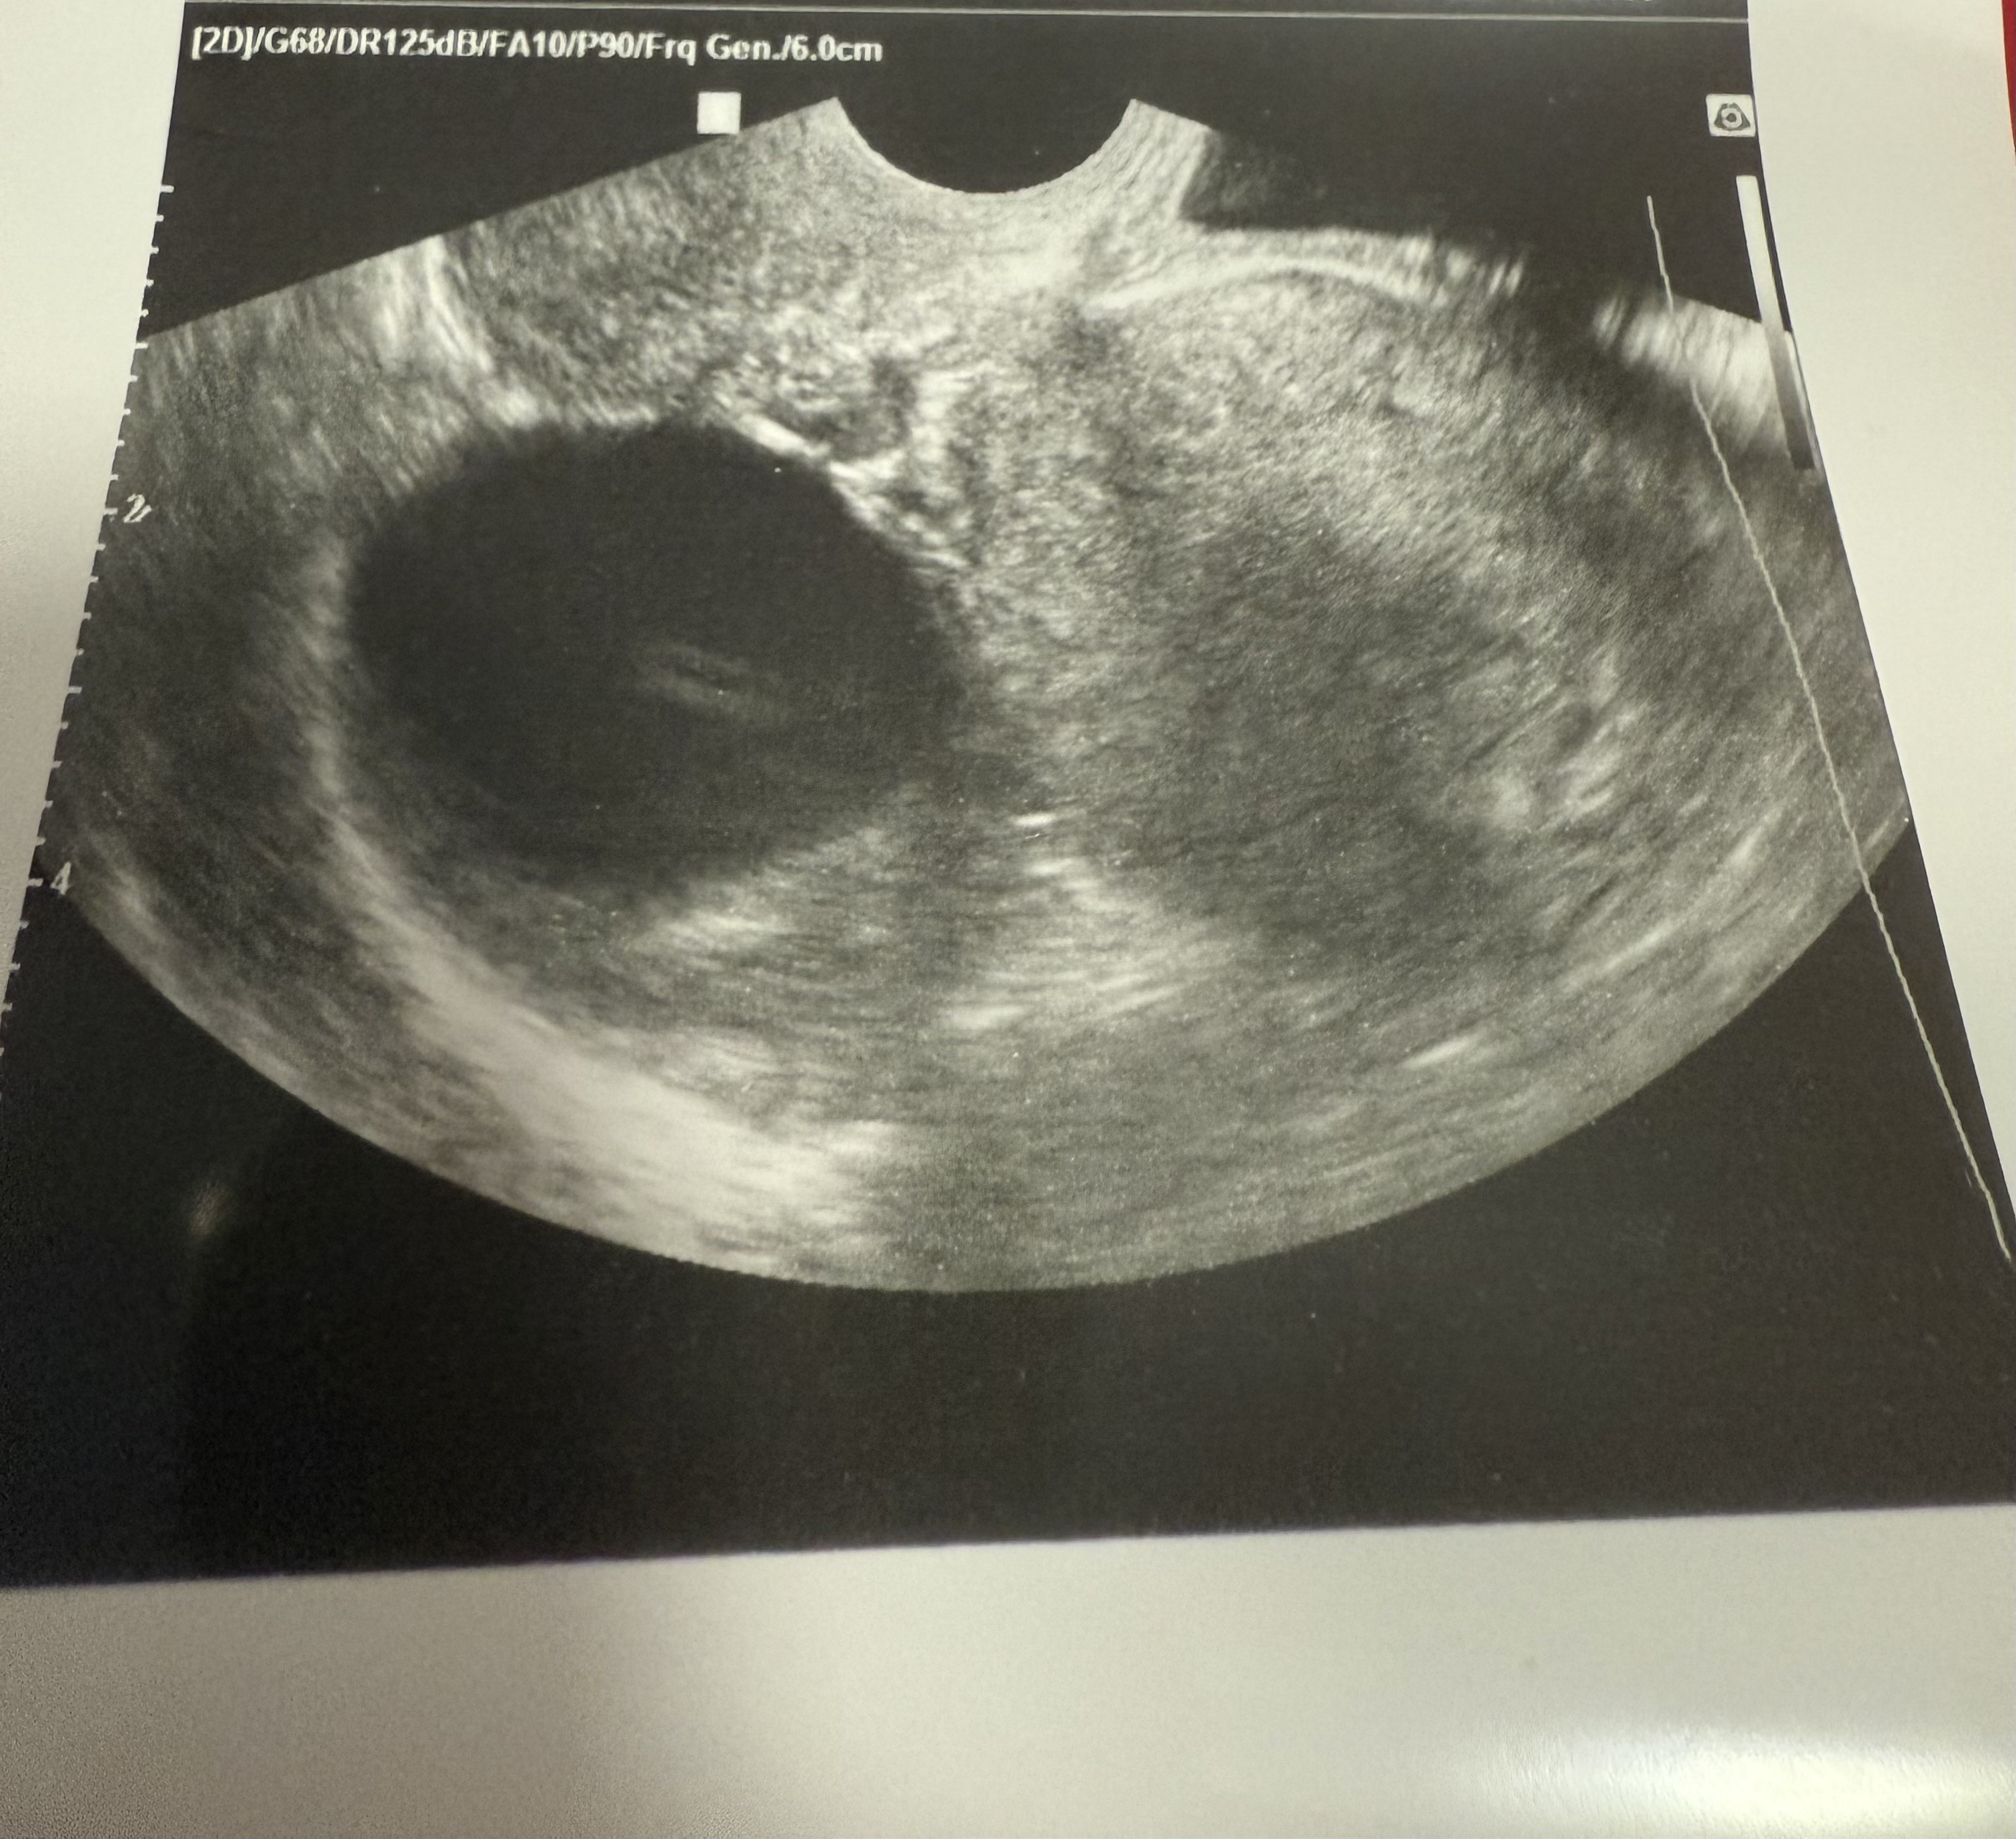

Oczywiście zapisałam sie do innego lekarza, dopiero na 25ego. Ten lekarz co byłam teraz przepisał mi duphaston i mowil ze mam brac acard oraz kwas foliowy ale to brałam juz przed ciąża. Zrobił mi usg ale ja za bardzo nie rozumiem .”zdania : Jest ślad po pecherzu ale nic nie widać jeszcze. To jak to interpretować? Wstawiłam usg moze jakas dziewczyna z was bedzie wiedzieć czy cos widać, jak to interpretować.

IMG_2328.jpeg

Załączniki

• IMG_2327.jpeg

IMG_2327.jpeg

1,2 MB · Wyświetleń: 36